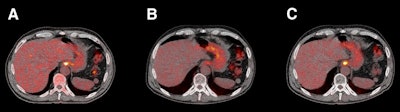

FDG-PET/CT at baseline (A), 12 weeks (B), and 24 weeks (C) after completion of neoadjuvant chemoradiotherapy. Initial clinically complete response at 12 weeks was followed by an increase in FDG avidity at 24 weeks. In view of these findings, esophagectomy was performed, and residual tumor was found in resection specimen. Resection was radical, and tumor margins were free of disease. Images courtesy of JNM."It is currently unknown whether it is safe to postpone surgery in patients with a minimal amount of residual tumor," wrote the authors, led by Dr. Maria Valkema from Erasmus University Medical Center in Rotterdam. "We expect that detection of tumor recurrence may be timely -- that is, within the window of opportunity (when complete resection is still possible) -- during systematic rigorous follow-up. However, the duration of this window of opportunity is probably limited."